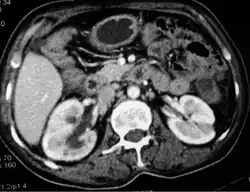

![]() Obraz zgrubiałej otrzewnej w tomografii komputerowej[1] | |

- tomografia komputerowa (zlokalizowane wodobrzusze, zrosty jelitowe, zwężenie jelit, zwapnienia w błonie otrzewnowej, pogrubienie błony otrzewnowej).